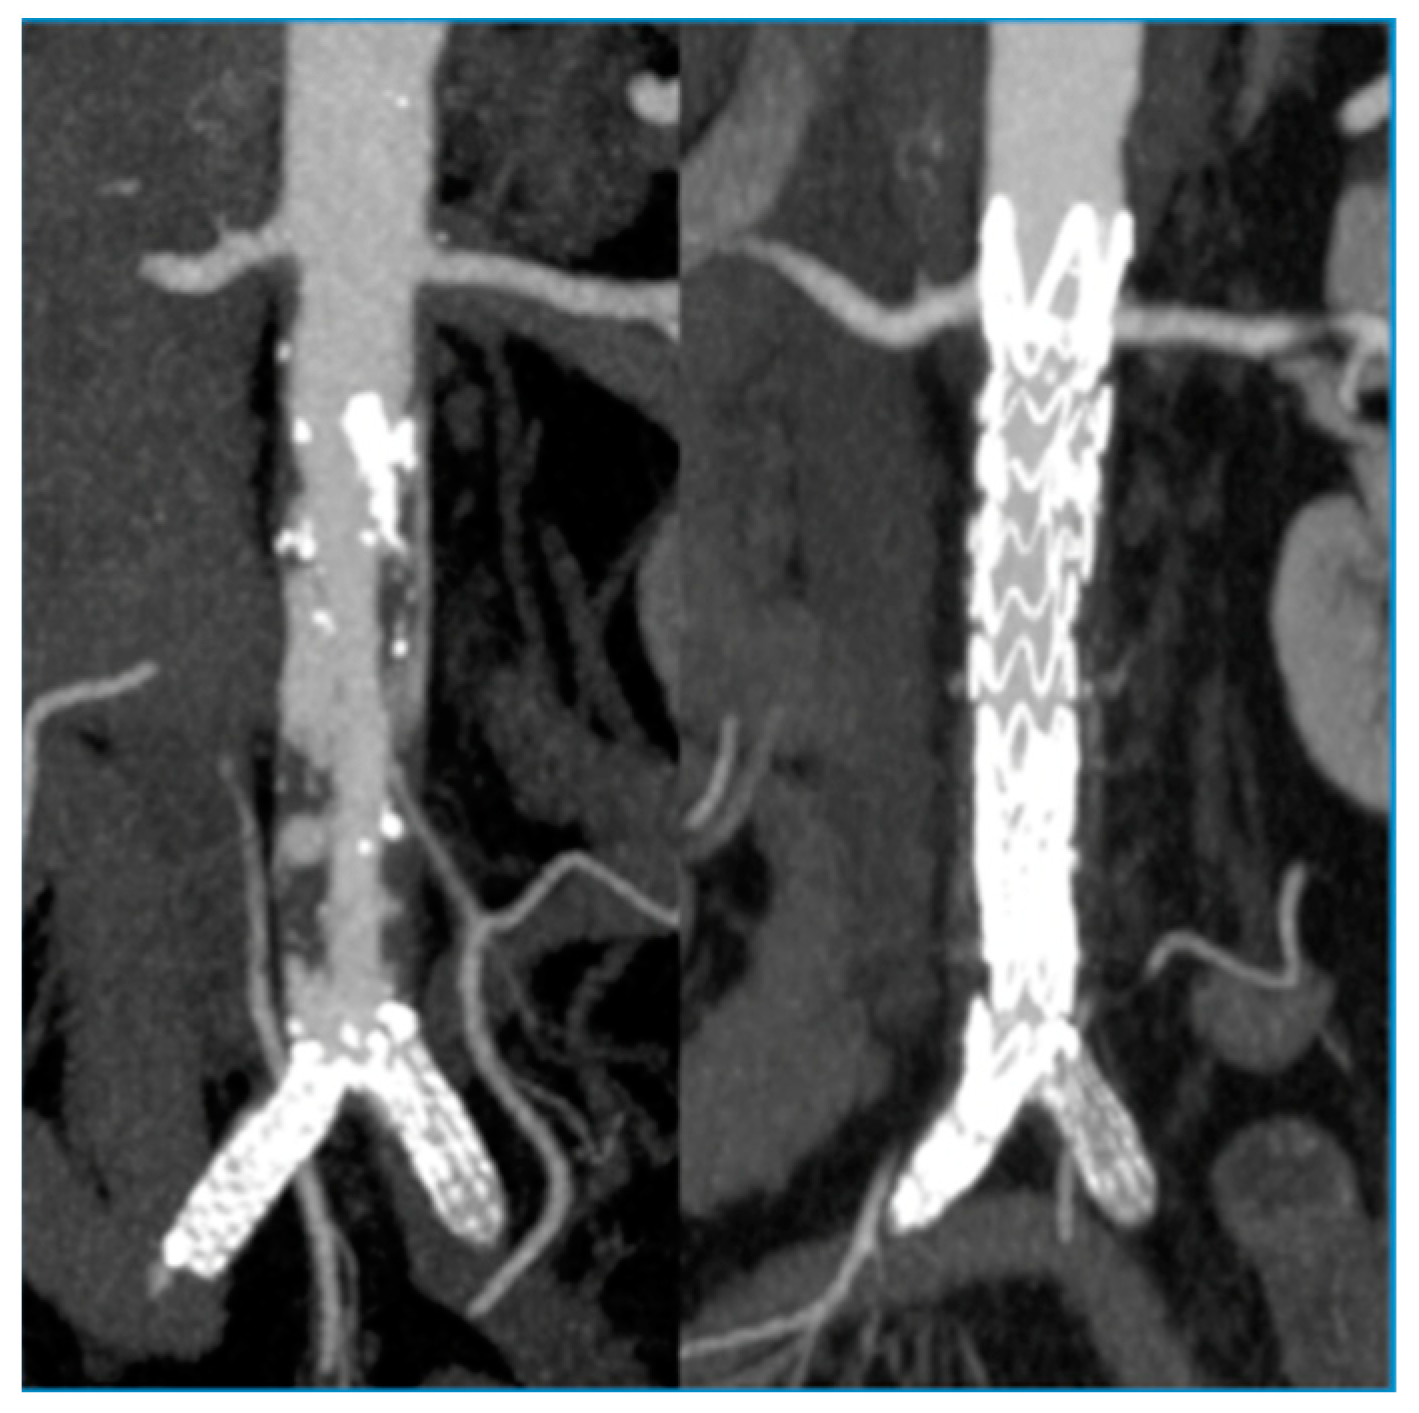

Single-Center Experience with Simultaneous Mural Aortic Thrombosis and Peripheral Obstructive Disease in Pre-COVID-19 and COVID-19 Era

3. Results

| Thoracic aortic source | 19 (35%) |

| Abdominal aortic source | 35 (64%) |

| Hybrid treatment | 30 (55%) |

| Aortic procedure only | 24 (44%) |